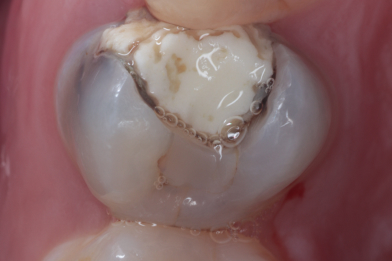

Д.12 лет. Жалобы на реакцию, на сладкое и холодное между зубами 16,15.

Колиш Максим Петрович

При осмотре обнаружен контактный кариес на зубах 16,15.

Лечение в один визит, восстановление функциональности композитной реставрацией. -